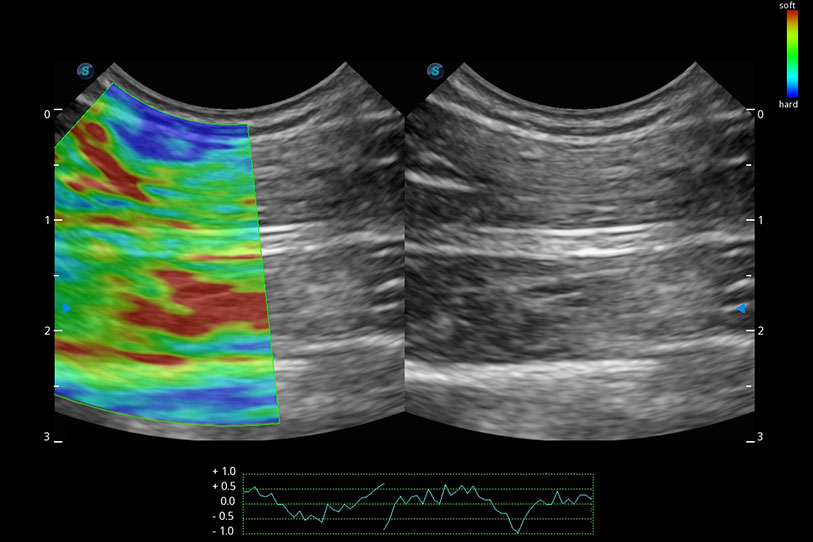

操作簡便,無需高頻度外力作用即可真實(shí)反映組織的形變,快速評估腫瘤良惡性。

實(shí)時(shí)用顏色表示心肌組織運(yùn)動,觀察和定量組織的運(yùn)動情況,對快速檢測與評估心肌的灌注和活性、電傳導(dǎo)及心肌收縮和舒張功能等均能提供重要的診斷信息。